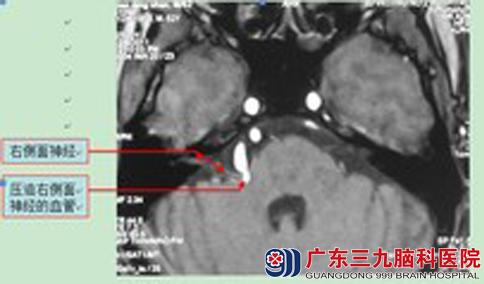

儿子心疼母亲,带着她来到广东三九脑科医院综合神经外科。头颅MRI检查提示:右侧面听神经颅内段起始部一小动脉影紧贴神经前缘走行并压迫邻近脑桥。鲁明主任告诉他们:结合病史及影像资料,考虑引起孟阿姨眼角、嘴角抽搐的和右侧小脑后下动脉可能性大。

鲁明主任主刀,在全麻下行右侧面神经微血管减压术,术中暴露面神经,见右侧小脑前上动脉压迫并伴行于面神经,小心分离血管,予Tefflon脑棉分离垫开并予胶固定。术后孟阿姨的眼角、嘴角抽搐症状完全消失,已康复出院。